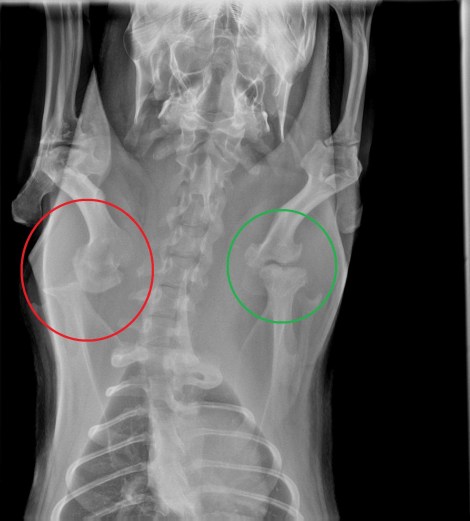

Melanie says “Pet capybaras that don’t get enough Vitamin C frequently develop scurvy. We have seen this over and over.” The first symptom we see is low weight gain, and for this reason the ROUS foundation recommends weighing your capybara regularly, as in monthly. Unseen, but more devastating is the structural damage that occurs. Bones do not develop properly, bending and lacking in strength. The skull may not develop the density needed to hold the enormous teeth in place. Scurvy in humans is often accompanied by bleeding gums, but in capybaras the teeth can fall out. The teeth themselves may also not develop proper strength and break easily. A low weight capybara with broken teeth almost surely has scurvy.

Because of early poor nutrition, Garibaldi ROUS’s skull density was not adequate to support his enormous capybara teeth.